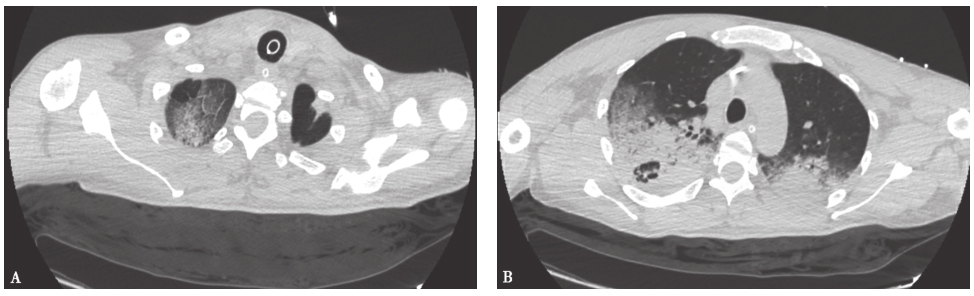

【影像学检查】

胸部CT:双肺多发大片磨玻璃及实变影,右肺上叶后段空洞形成,双侧胸腔积液(图2)。

图2 发病第7天胸部CT表现